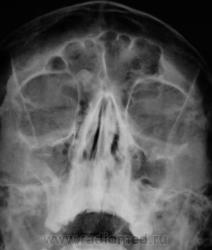

Касательно пристеночного уплотнения справа в в/ч пазухе- вполне возможно суммационное искажение из-за неправильной укладки,с учетом клиники-я бы перестраховался и назначил томограмму(в идеале-малодозовый режим СКТ на ППН). Можно назначить контроль в динамике.

что-то плотное в правой лобной пазухе- остеома?

Образование правой лобной пазухи,пристеночное утолщение слизистой пр.гайморовой пазухи. Как всегда может помочь томограмма.

Остеома с типичной локализацией. Неосложненная.